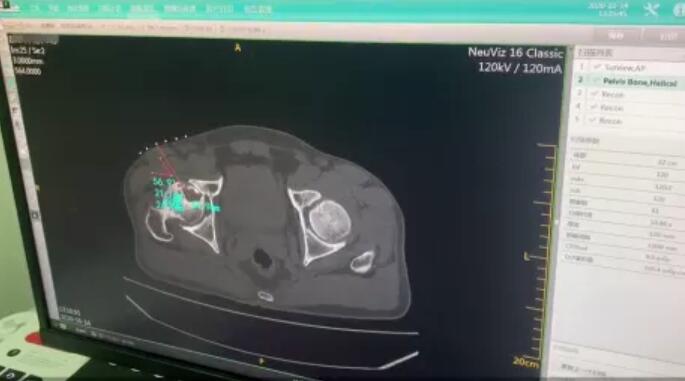

CT辅助、精准定位坏死灶,确定穿刺路径

在专业CT检测下,精准定位坏死灶,确定并计算好微创穿刺位置与角度。确保治疗的精准有效以及手术的安全。